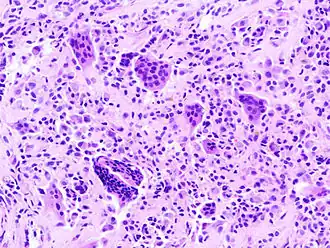

Histopathologie van PVNS

SVP valt onder de reumatische aandoeningen. Het kenmerkt zich als een aanhoudende/chronische gewrichtsvlies-ontsteking waarbij pigment-korrels worden gevormd. Deze pigmentkorrels zijn een woekering van "goedaardig" weefsel en kunnen schade toebrengen aan het gewricht. De pigmentkorrels kunnen zich in het bot "vreten". Kortgezegd heeft men last van een goedaardige tumor.

Over de aandoening is weinig bekend. De symptomen zijn: zwelling en stijfheid van het gewricht en pijn. De symptomen hebben veel weg van reumatische klachten. Deze aandoening kan vaak alleen aangetoond worden door middel van een Magnetic Resonance Imaging (MRI-scan of het histologisch onderzoek van weefsel, na biopsie.